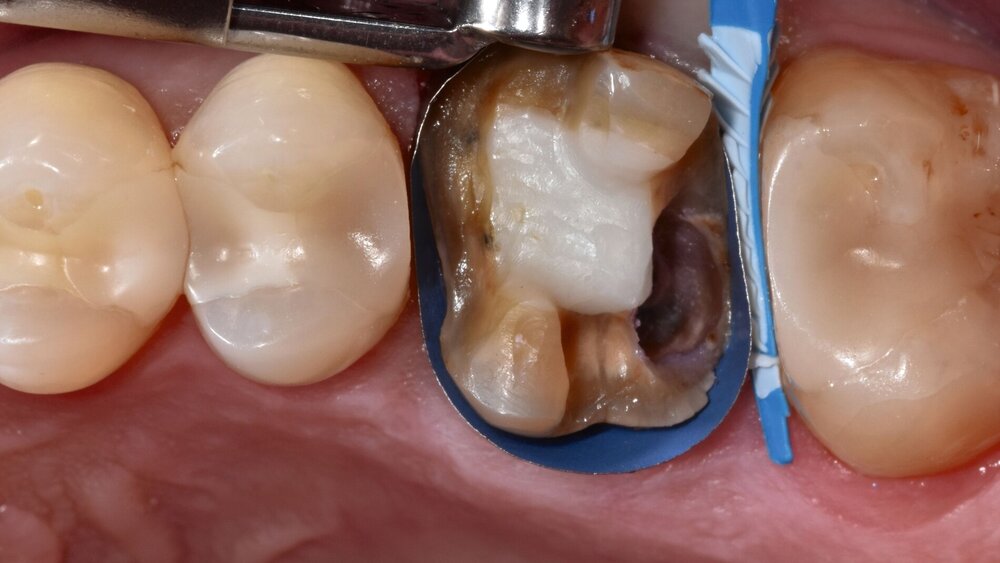

Zahn 26 ist vor etwa 20 Jahren endodontisch behandelt und anschließend postendontisch mit einer indirekten keramischen Restauration versorgt worden. Bei der klinischen und der röntgenologischen Diagnostik fällt distal an Zahn 26 eine bis in den subgingivalen Bereich reichende Sekundärkaries auf. Die Wurzelkanalfüllung erscheint homogen und randständig, es besteht kein Hinweis auf eine periapikale Osteolyse. Weiterhin besteht kein Anhalt auf eine parodontale Erkrankung. Bis zur definitiven restaurativen Therapie wird das freiliegende Dentin mit einer Schicht Flow-Komposit abgedeckt (Abbildung 1).

Zu Beginn werden die frakturierte Teilkrone und das provisorisch aufgebrachte Flow-Komposit entfernt, der kariöse Defekt dargestellt und die Wurzelkaries exkaviert. Mit einem speziellen 10-Methacryloyloxidecyl-Dihydrogenphosphat(MDP)-haltigen Cleaner wird das mit Speichel kontaminierte Wurzeldentin gereinigt und für die Adhäsivtechnik vorbereitet (siehe Materialliste). Im hier gezeigten Fall kann trotz des subgingivalen Defekts zirkulär eine spezielle Ringbandmatrize angelegt werden, die zusätzlich mit einem Keil abgedichtet wird.